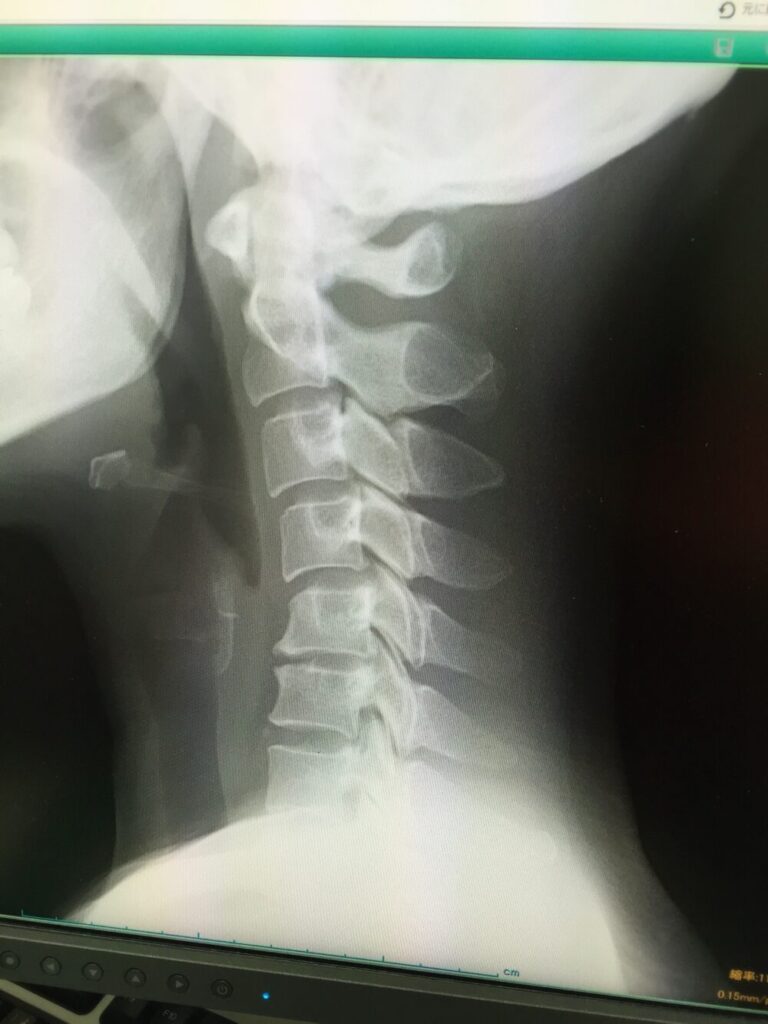

8.1.2 画像診断による確認

触診だけではわからない、体の内部の状態を確認するために、以下のような画像診断が行われることがあります。

- レントゲン検査

首の骨の配列や変形、骨棘(骨のトゲ)の有無、ストレートネックの程度などを確認します。 - MRI検査

椎間板の状態、神経の圧迫具合、炎症の有無などを詳しく見ることができます。頸椎ヘルニアの診断には特に有効とされています。 - CTスキャン

骨の詳細な構造や神経が通る脊柱管の狭窄(狭くなっている状態)などを立体的に確認するのに役立ちます。